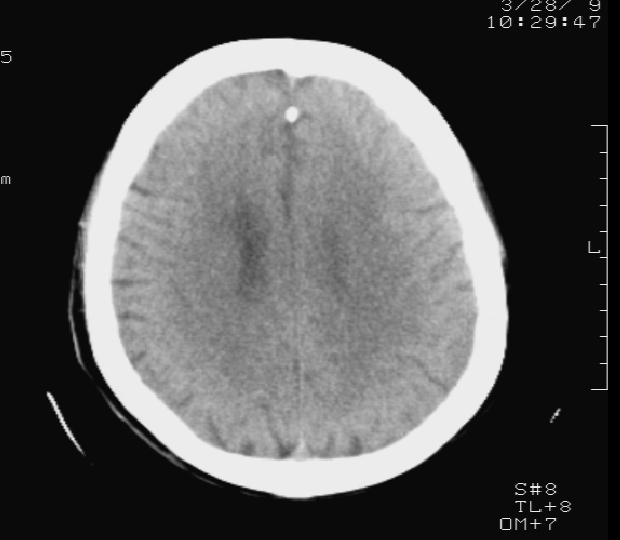

标题: CT19079:出血?钙化?(已证实为出血) [打印本页]

标题: CT19079:出血?钙化?(已证实为出血)

男 58岁 双下肢无力个一天 糖尿病患者

测ct值 67左右

患者今日行mr检查:右侧室管膜下见条状短t1长t2 flair呈高信号影, 证实为出血

灶周水肿,ct值较低,考虑室管膜下出血

考虑室管膜下出血;建议短期复查,排除钙化灶。

考虑室管膜下出血,因为旁边有水肿。